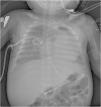

At 2 months and a half, follow-up radiographs started to show periosteal thickening of the long bones (Fig. 1) with gradual progression (Fig. 2). Hypervitaminosis A and D and congenital syphilis were ruled out as potential causes of the lesions. The patient underwent measurement of alkaline phosphatase at different timepoints, with levels peaking at 935 U/L at age 4 months (normal range for age, 85–235 U/L).

Plain radiograph at age 2.5 months. It is the first radiograph of the patient that showed cortical thickening, which was more evident in the diaphyses of both humeri (arrow), relative to the original appearance of the bones. Thickening was also apparent in other bones including ribs, the clavicles and the scapulae.